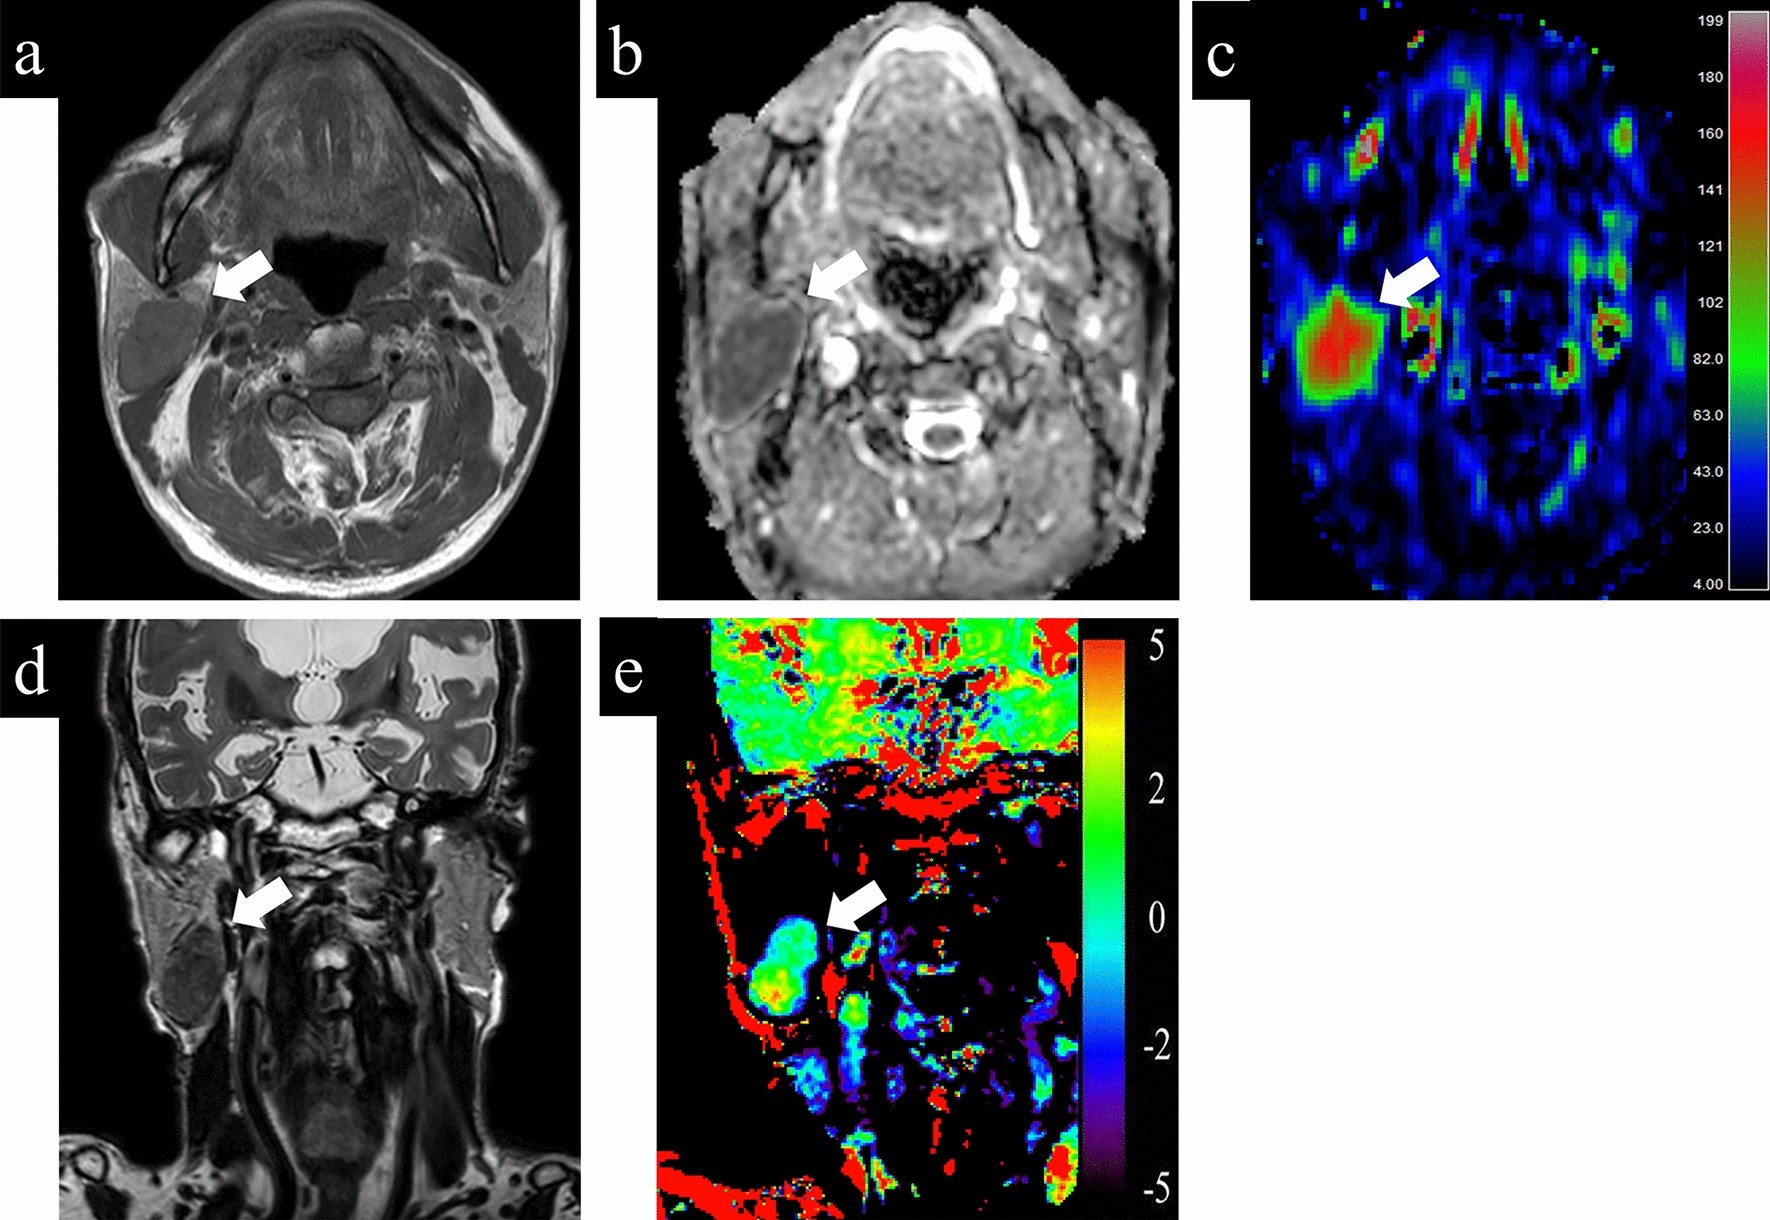

Figure 5

A 79-year-old male with Warthin tumor. (a) T1-weighted image shows a homogeneous low intensity lesion in the right parotid gland. Apparent diffusion coefficient (ADC) (b) and tumor blood flow (TBF) (c) maps show the lesion with the mean ADC value of 0.85 × 10−3 mm2/s and the mean TBF value of 133.06 mL/100 g/min, respectively. On T2-weighted coronal image (d), the lesion shows lower signal intensity than the adjacent parotid gland parenchyma. Amide proton transfer (APT) (e) map shows the lesion with the mean APT-related signal intensity of 1.24%. An arrow in each image indicates the lesion.